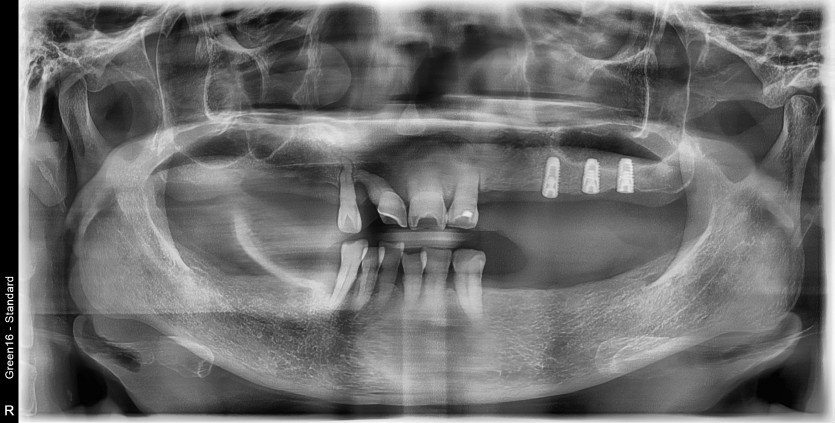

만 58세 전체 임플란트 증례입니다.

18개의 임플란트로 완성하였습니다.